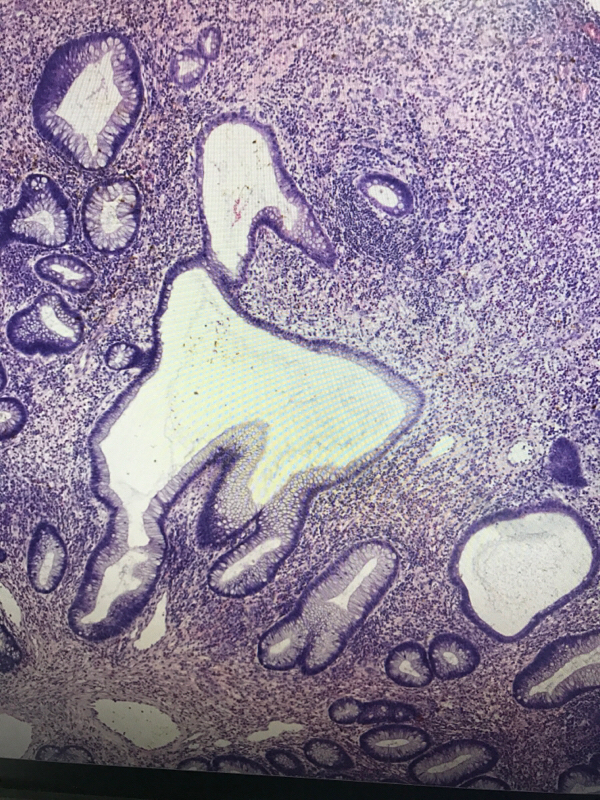

直肠息肉

一般病史

血便4天

灰红结节一枚,大小1✖️0.6✖️0.6cm,切面灰红,质软

管状腺瘤,低级别还是高级别?

幼年性息肉,灶性低级别

幼年性息肉?

幼年性息肉